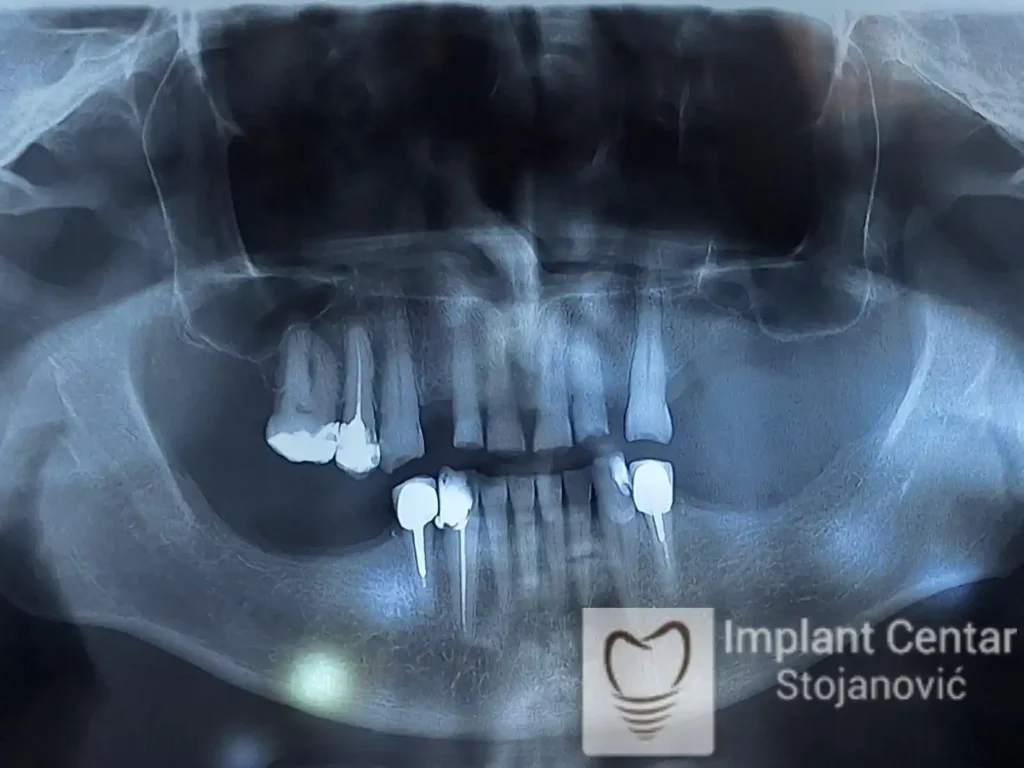

Na slici 1. i slici 2. prikazan je izgled pacijenta pre početka terapije – klinički i rendgenološki.

Nakon vađenja zuba, ugrađeni su implantati. Na slici 3 prikazan je ortopan snimak sa ugrđenim implantatima. Tokom perioda osteointegracije, pacijent je bio zbrinut fiksnim privremenim krunicama na implantatima, koje su izrađene samo dva dana nakon hirurške intervencije.